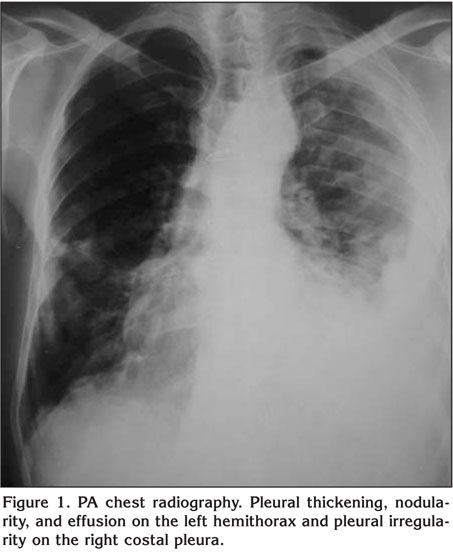

• Pseudochylotorax Without Pleural Thickening Associated With Rheumatoid Arthritis Archivos De Bronconeumologia English Edition